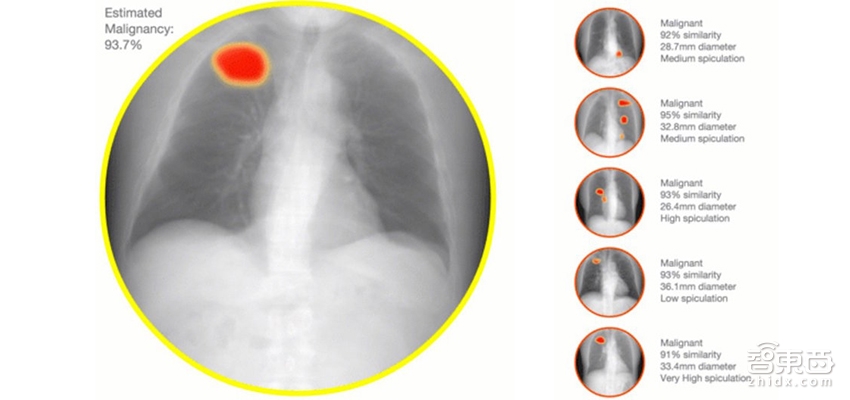

下一步,医拍智能将业务拓展至拓CT、X光、病理切片等医疗影像的识别与诊断。医拍智能医学影像AI系统结合了最新的深度学习算法,在人类医生的帮助下,通过对大量医疗图像数据进行解析,自动总结出能够代表恶性肿瘤的“形状特征”以及形成能够用来判断有无恶性肿瘤的“识别模式”。AI系统将其总结出的识别模式应用于医学影像中时,便可判断影像中是否存在恶性肿瘤,且准确度和判断速度超越了传统方式。